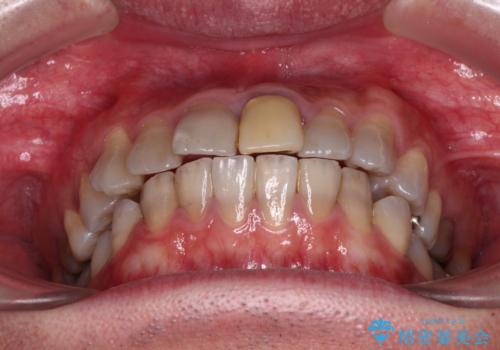

- 飛び出した前歯を気にして来院された患者様です。

口元を引っ込めるために上下左右の第一小臼歯4本を抜歯することとしました。

特徴的な歯の色が気になっているとのことで、今後セラミッククラウンによる審美歯科治療を検討されているとのことで、矯正治療の後戻りが落ち着いたタイミングで治療を進めていく予定です。